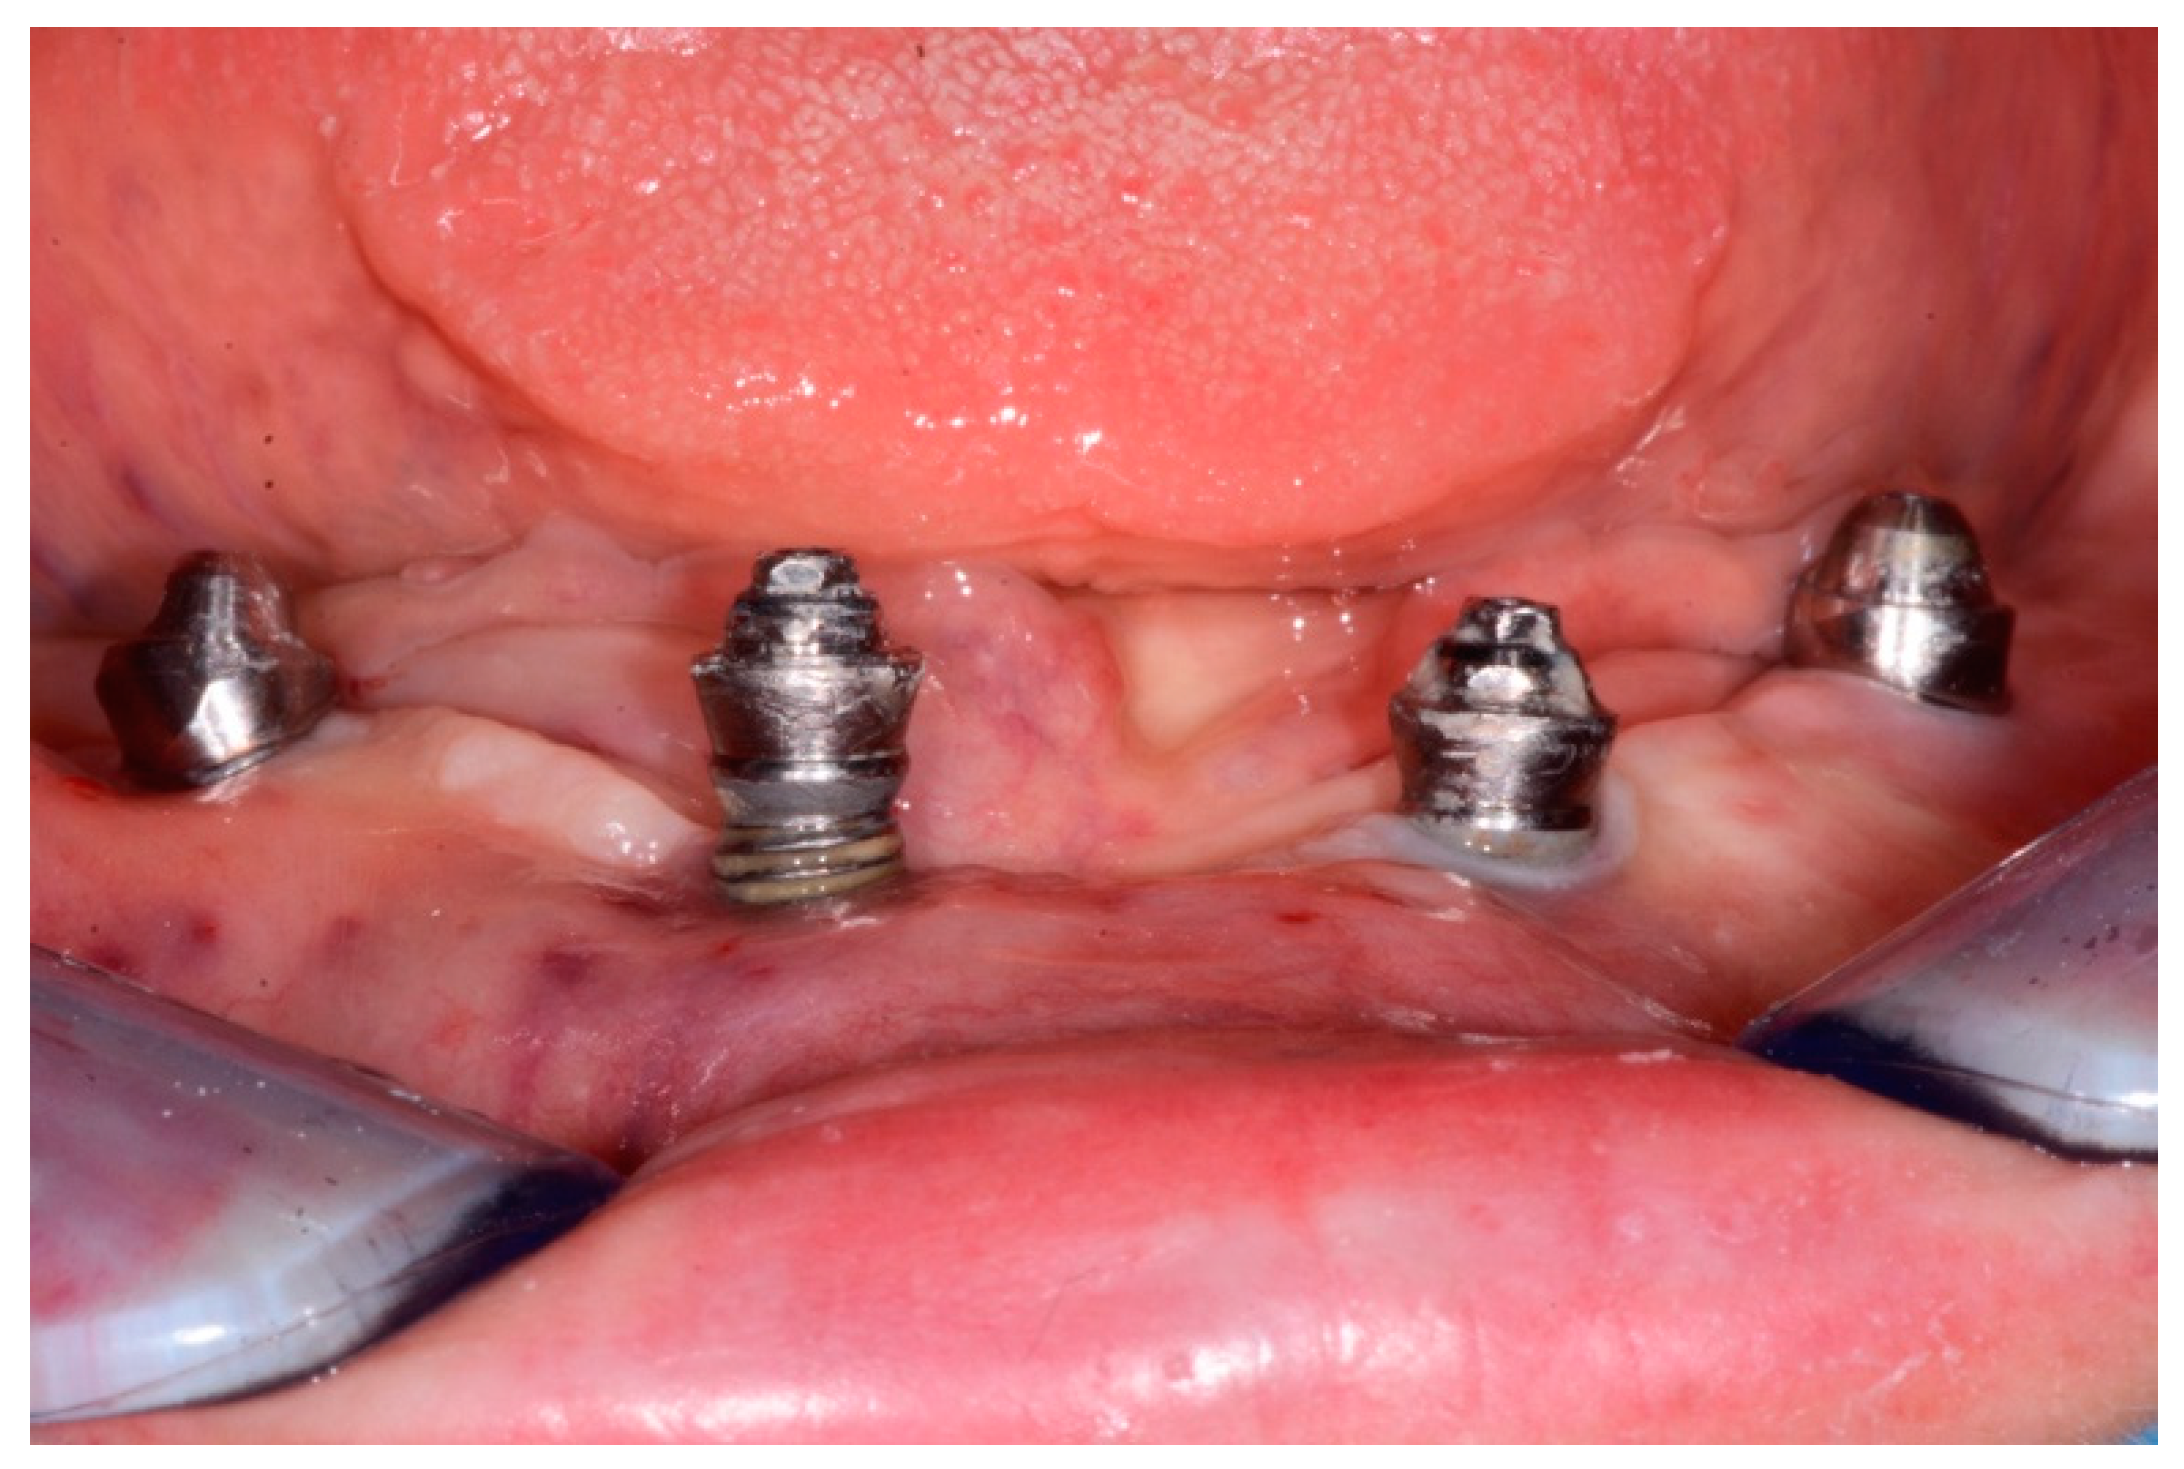

A total of 23 cases of peri-implantitis (patient-level) were registered, representing an overall prevalence of 11.3%. Only one diabetic patient (type 2) developed peri-implantitis (5.3%) whereas one subject with type 1 diabetes experienced multiple implant failures due to a failure of osseointegration. Figure 1 and Figure 2 show radiographic evidence of peri-implantitis in one diabetic (Figure 1) and one non-diabetic patient (Figure 2). Figure 1 and Figure 2 show radiographic evidence of peri-implantitis in one non-diabetic (Figure 1) and one diabetic patient (Figure 2). A clinical image of the same diabetic patient is represented in Figure 3.

Figure 3.

Clinical photograph of the same diabetic patient, showing suppuration and exposure of the implant threads.